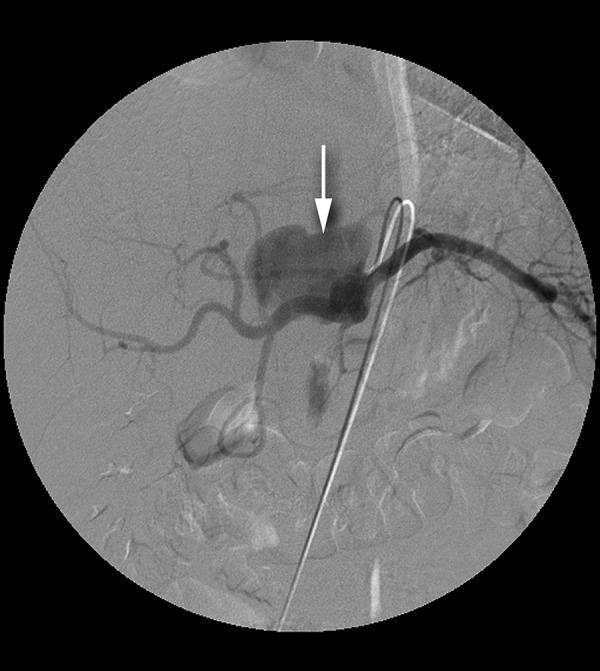

A 22-year-old man, who had undergone gastric, pancreatic and aortic surgery 2.5 years earlier, presented with progressive abdominal pain. Multidetector computed tomography scan revealed an 8-cm celiac pseudoaneurysm. We report a giant celiac pseudoaneurysm treated with stent-graft implantation.

Endovascular treatment of VAA is a safe and effective method alternative to surgery.